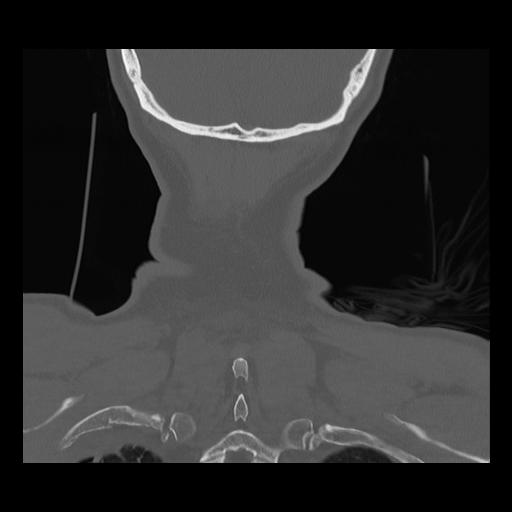

16 HUESO,,Coronal,2.000,HUESO,Coronal,